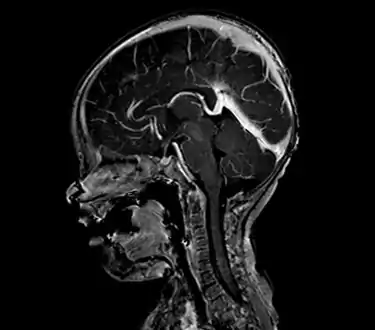

| Large arteriovenous malformation of the parietal lobe | |

An AVM diagnosis is established by neuroimaging studies after a complete neurological and physical examination.[5][11] Three main techniques are used to visualize the brain and search for AVM: computed tomography (CT), magnetic resonance imaging (MRI), and cerebral angiography.[11] A CT scan of the head is usually performed first when the subject is symptomatic. It can suggest the approximate site of the bleed.[3] MRI is more sensitive than CT in the diagnosis of AVMs and provides better information about the exact location of the malformation.[11] More detailed pictures of the tangle of blood vessels that compose an AVM can be obtained by using radioactive agents injected into the blood stream. If a CT is used in conjunctiangiogram, this is called a computerized tomography angiogram; while, if MRI is used it is called magnetic resonance angiogram.[3][11] The best images of an AVM are obtained through cerebral angiography. This procedure involves using a catheter, threaded through an artery up to the head, to deliver a contrast agent into the AVM. As the contrast agent flows through the AVM structure, a sequence of X-ray images are obtained.[11]